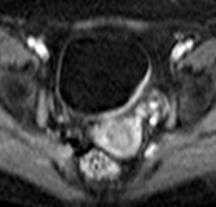

Неинвазивная уротериальная карцинома.

а) Т2-аксиальное изображение б) DW-аксиаальная плоскость

Мужчина, 49 лет, уротелиальная карцинома.

а) Т2-взвешенное изображение показывает опухоль с тканевой интенсивностью МР-сигнала на заднее-левой стенке мочевого пузыря. При этом видно легкое повышение интенсивности МР-сигнала от гипоинтенсивной в норме стенки пузыря (стрелки). (б Диффузинно-взвешенное изобрежение показывает опухоль (тонка стрелка) и ее распространение в подслизистый слой (головки стрелок), без признаков инвазии в мышечный слой.